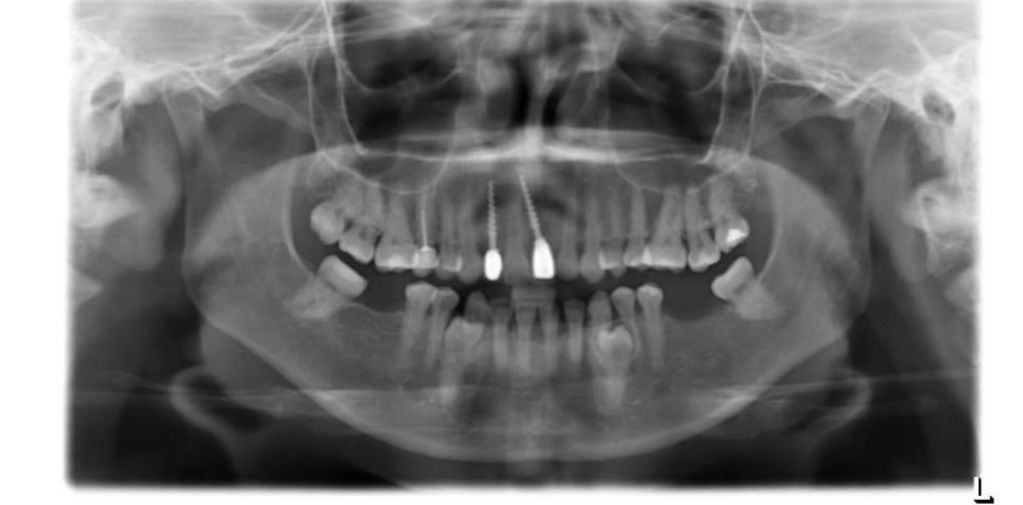

En la Rx. Panorámica de diagnóstico observamos ausencia de los diente 12 y 21 con una atrofia ósea severa, razón por la cual, ya le habían dicho al paciente en otras clínicas odontológicas, que necesitaba injertos óseos y un tiempo de tratamiento de 1 año.

Observamos la Rx. Panorámica de control donde podemos apreciar los dos implantes en posición, según la planificación realizada para este caso de alta complejidad.